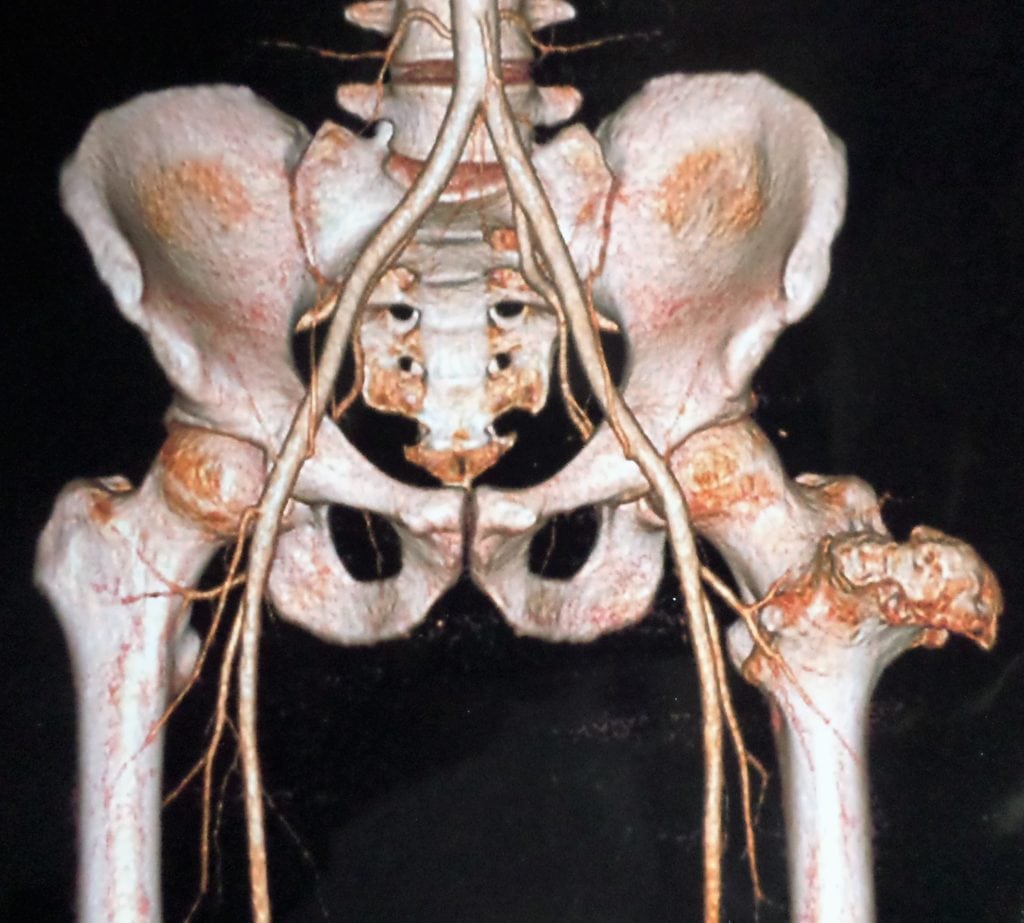

Совокупность симптомов и результаты инструментальных исследований становятся основанием для выставления диагноза. Ведущая методика — рентгенография. Для оценки состояния мягких тканей, связок, мышц, сухожилий, нервов и кровеносных сосудов проводится МРТ или КТ.

На рентгенографических изображениях хорошо просматриваются измененные контуры бедренной кости. Визуализируются и очертания новообразования — четкие, непрерывные. С помощью рентгенологического исследования не удается рассмотреть сформировавшуюся хрящевую оболочку, только если в ней нет очагов кальцификации. При подозрении на укрупнение хрящевого слоя пациентам назначается МРТ.

Дифференциальная диагностика проводится для исключения остеомы, паростальной остеосаркомы, паростальной костно-хрящевой пролиферации и хондросаркомы, возникающей вследствие озлокачествления остеохондромы.